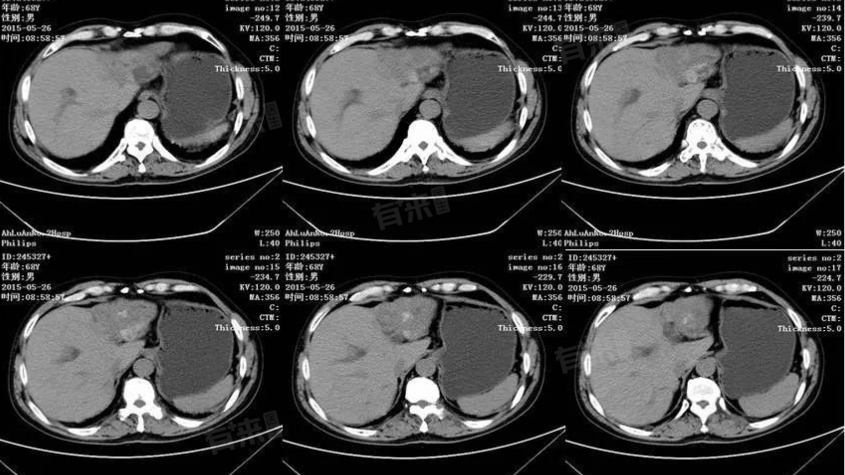

肝低密度灶是在肝脏影像学检查中发现的一种异常表现,指肝脏内出现密度低于正常肝组织的区域,可能由脂肪肝、肝囊肿、肝血管瘤、肝脓肿等多种原因引起,需综合诊断明确病因。

2、肝囊肿:肝囊肿通常是由于先天发育异常或后天的创伤、炎症等引起,囊肿内部充满液体,在CT上表现为边界清晰的低密度灶,多数肝囊肿较小且无症状,定期复查即可,若囊肿较大,可能会压迫周围组织,引起腹痛、腹胀等症状。

3、肝血管瘤:属于肝脏的良性肿瘤,多由血管内皮细胞异常增生形成,血管瘤在CT上通常表现为边界清晰的低密度灶,增强扫描时有特征性的强化表现,小的肝血管瘤一般无需治疗,较大的血管瘤若有破裂出血风险或引起明显症状,可能需要手术或介入治疗。

5、肝癌:恶性肿瘤也是导致肝低密度灶的原因之一,尤其是早期肝癌或小肝癌,在CT上可表现为低密度灶,但肝癌的密度多不均匀,形态不规则,且常伴有肝硬化背景,进一步的增强扫描、肿瘤标志物检测及病理活检有助于明确诊断,需要进行手术、化疗等处理方式。